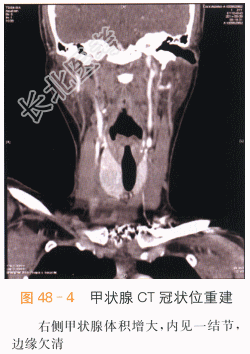

影像学资料如图48-1~图48-4所示。

本案例CT扫描见右侧甲状腺增大,结节与正常甲状腺分界不清,呈低密度,见沙砾样钙化(见图48-1),增强后呈低度强化,甲状腺包膜不完整,(见图48-2~图48-4),结合超声检查,考虑甲状腺癌。